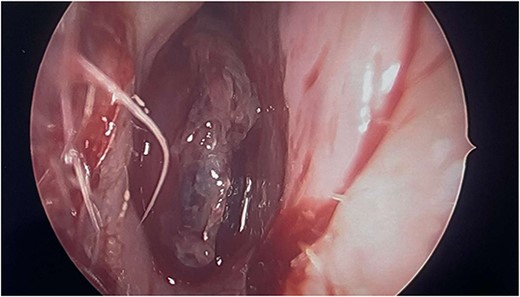

Complete head and neck examination, including flexible nasal endoscopy, revealed a nasal mass emanating from the right maxillary sinus. There was no active bleeding or purulence on his physical exam. The physical exam of the contralateral side was unremarkable. CT scan of the sinuses with IV contrast revealed an expansile soft tissue mass measuring 4.1 × 2.4 × 3.3 cm. The mass involved the middle turbinate and expanded to the medial wall of the maxillary sinus, blocking the right osteomeatal complex. There was evidence of mucosal thickening of the right ethmoid, right frontal, and right maxillary sinus as well as right septal deviation (Figs 1 and 2). Differential diagnosis based on the physical exam and imaging included inverting papilloma, polypoid mass, vascular lesion, malignant neoplasm, and even an infectious process. The patient was scheduled for functional endoscopic sinus surgery with excision of right nasal cavity mass, right frontal, and maxillary sinuplasty as well as ethmoidectomy and possible septoplasty at the ambulatory surgery center.

Intraoperatively, the right nasal mass appeared hyper vascular (Fig. 3) and bled easily with manipulation. After adequate anesthesia, a zero-degree endoscope and microdebrider were used to take down the right nasal cavity mass. Significant bleeding was encountered during extirpation. The bleeding was successfully stopped via cauterization with suction Bovie and bipolar cautery and topical adrenaline application. Hemostatic packing was placed into the right nasal cavity in order to ensure ongoing hemostasis. At this time, it was determined to no longer be safe to continue the procedure as the patient had lost almost 350 cc of blood and there was concern for recurrent hemorrhage with further manipulation. The decision was made to terminate the procedure and to await biopsy results of the mass prior to further attempts at resection.